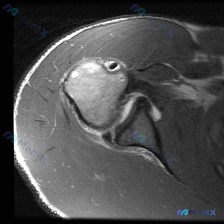

看到一个肩部MRI的病例资料,轴位T2加权图像显示前下盂唇区域有异常高信号改变,形态失去正常紧贴关节盂缘的三角形结构,呈现分离或变平的表现,关节腔还有少量积液。 大家看这个盂唇异常更像什么?是创伤性Bankart损伤,还是正常的解剖变异(比如孟氏孔)?

整理了一个肩部MRI轴位T2序列的病例,重点观察盂唇病理改变。影像显示: - 前下方盂唇区域(对应Bankart损伤好发区)有显著的高信号裂隙,将盂唇与关节盂前缘骨性结构分离,信号强度接近关节腔积液 - 肱骨头、关节盂骨质完整,无水肿或破坏 - 肩胛下肌腱连续,信号均匀 - 盂肱关节间隙少量积液 这...

看到一份肩关节MRI的病例资料,轴位T2加权像显示前下盂唇有明显的线状高信号,形态略显钝圆、不规则。报告里提到这个位置的病变可能是Bankart损伤,但也需要和正常解剖变异或退变性损伤鉴别。大家看看这个影像特征,更倾向于哪种诊断?

最近看到一份肩关节MRI轴位T2图像的病例,整理出来和大家讨论。 影像显示前盂唇区域有明显异常高信号,形态不规则,还和关节内液体信号相通,但后盂唇是正常的低信号三角形结构。关节腔有少量积液,骨质看起来也没明显问题。 大家来分析下,这个前盂唇的高信号最可能是什么病变?有哪些需要进一步明确的地方?

最近看到一份肩关节MRI轴位T2加权图像的分析,分享出来和大家讨论一下。 影像所见: - 前下方盂唇区域有局限性T2高信号,形态略显模糊 - 关节腔内有少量积液,表现为T2加权下的高信号影 - 肱骨头、结节间沟、肩胛下肌等结构未见明显异常 - 无明确骨或肩袖肌腱损伤的征象 讨论焦点: 前下方盂唇的T...